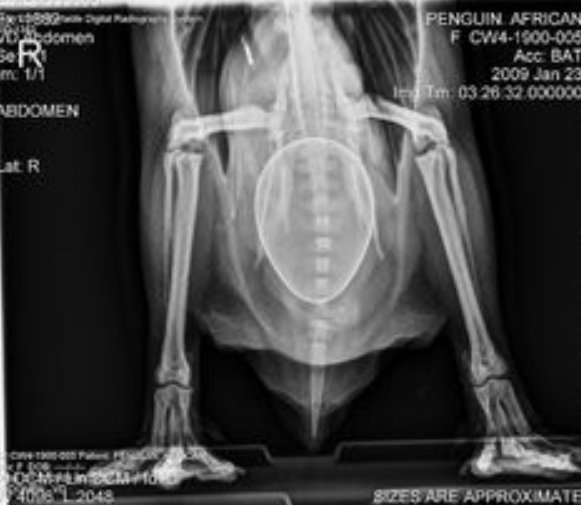

مجموعة من الصور بالأشعة السينية لبعض الحيوانات، معظمها في حالة الحمل.

الصور بالفعل مذهلة، سبحان الله العظيم.

6️⃣ بطريق حامل.